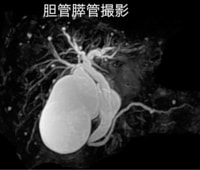

MRIの画像